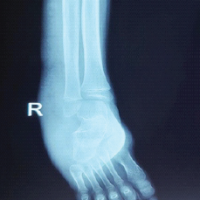

Radiological results were assessed using the Sarmiento radiological score. As presented in Table 2, 29 patients had excellent results, and one had a good outcome.

- Radiological maintenance (Sarmiento score): Near-anatomical alignment was preserved in most cases[Fig. 7]

Radiological outcome (Sarmiento score)

- According to the Sarmiento radiological scoring system:

- Excellent outcomes were observed in 29 patients (96.7%)

- Good outcome in 1 patient (3.3%).

- The one patient with a good score had a minor loss of radial length and palmar tilt but retained functional use.